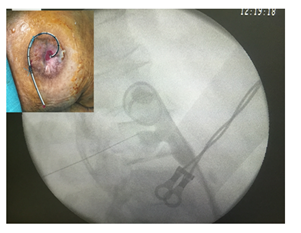

The patient is in a strict lateral position. After administration of 10 ml xylocaine, a kidney puncture is made under fluoroscopic guidance using a 22G Chiba needle (Figure 1A). Opacification of the collecting system permits to localise and observe the severity and length of the stricture. A second puncture is made using an 18G Chiba needle directly in the upper calyceal group, sometimes above the 12th rib. A hydrophilic 0.35-mm guide wire is introduced through the needle into the renal pelvis and ureter in antegrade fashion until it reaches and passes through the stricture (Figure 1B). The guide wire exits then through the ileostomy (Figure 1C). A 5F, 6F, 7F, and 8F ureteral stents are inserted on the guide in retrograde fashion to dilate the stenosis. Finally, a 7F single-J stent was placed and left in place (Figure 2). The patient remains under observation for 4hours and is then discharged. The stent is replaced every 9months in a retrograde manner through the ileostomy and under fluorescence guidance, on an outpatient basis.

Figure 2 7F single-J stent placed in retrograde fashion through the ileal conduit and left in place.